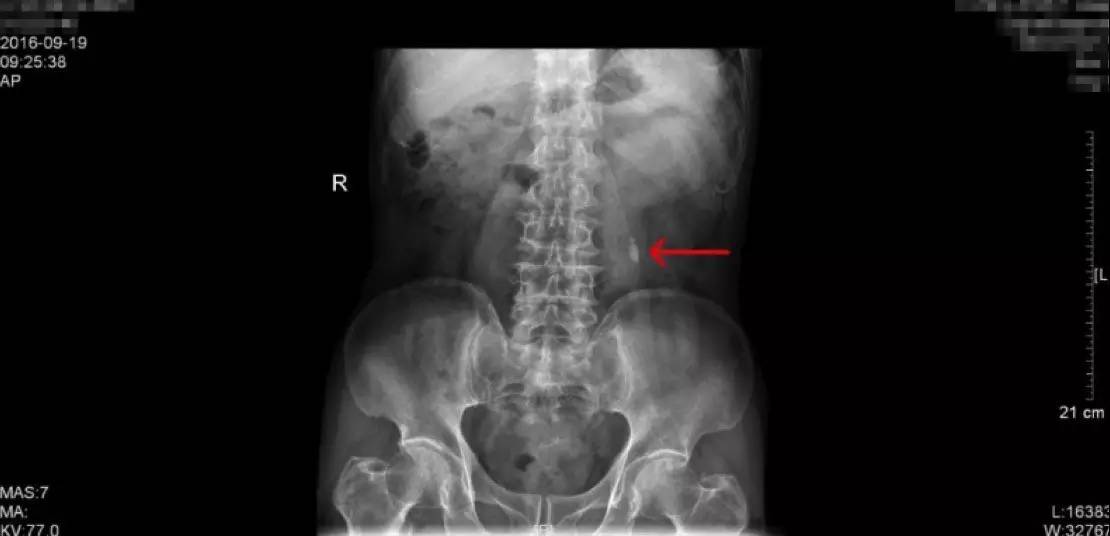

KUB检查报告:结石最大为1.2cm

KUB这一检查是泌尿系结石的常规检查之一,学名称为泌尿系平片,一般是指患者在经过肠道准备后(前一天服用泻药,让肠道内容物排出,第二天禁食,以减少肠道内容物对影像的干扰),在X线透视下摄片,涵盖整个泌尿系统,包括肾、输尿管、膀胱区域,观察这一区域有无阳性结石(酸性结石,尤其纯的酸性结石在X下无法显现,我们称为阴性结石,这一检查就无法看到,但比较少)。这一患者的KUB检查片子如上,能够看到,阳性结石表现为白色的强化,就是片子中红色箭头所指的地方,一般患者手术后也要拍一张KUB,能够和术前的检查相对比,从而直观的确认手术的效果。